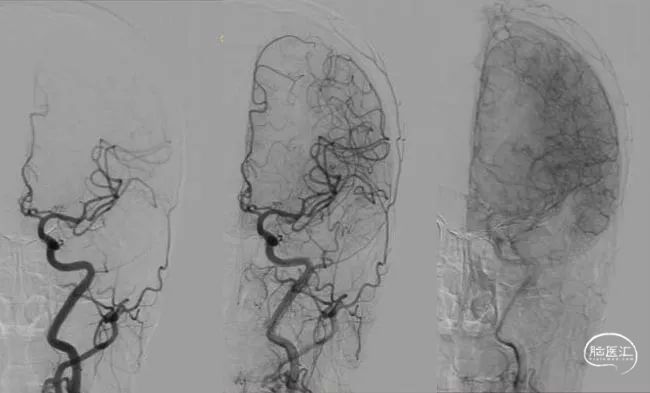

没有颅内出血,急诊复查造影,左侧颈动脉支架内通畅,左侧前循环颅内动脉显影良好,再次除外急性脑梗死,给与静脉乌拉地尔控制血压、甘露醇脱水降颅压治疗后,患者病情稍有缓解,NIHSS 12分,同时查灌注成像(图5)、TCCD(图6)未提示术后高灌注表现。

图5:DSA下行脑灌注检查(到达时间、达峰时间)双侧无明显差异

图6:复查造影时行TCD检查

患者转至监护室继续控制血压、脱水降颅压治疗,病情逐步好转。次日复查头颅核磁(图7),脑肿胀明显减轻,但DWI也提示在左侧半球散在点状高信号,核磁灌注成像(图8),双侧半球基本对称。TCD(图9)提示左侧半球血流速度正常。

图8:核磁灌注成像,双侧无差异

图9:术后第二天复查TCCD